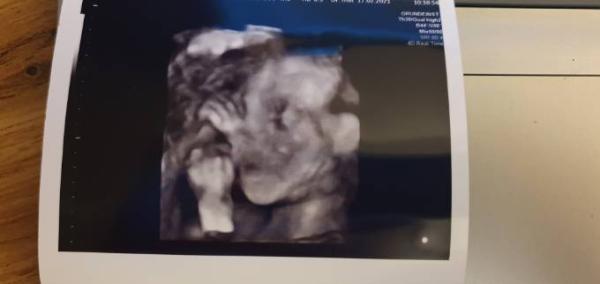

Ich war heute bei der Feindiagnostik - alles super mit der Kleinen, ich bin megaglücklich . War aber ganz schön anstrengend, da wir die Untersuchung drei mal unterbrechen mussten, weil die Maus so ungünstig lag. Also Treppen steigen, Süßes essen, hinlegen, alles probiert und beim dritten Anlauf lag sie dann besser . Der Arzt hat dann tun Schluss noch auf 3D geschaltet, oh mein Gott, das war schon ergreifend. Jetzt zuhause fällt mir auf, dass die Nase vom Baby ganz schön brummig aussieht und auch andere Proportionen verzerrt wirken. Habt ihr diese Beobachtung auch gemacht?

Guten Abend Das ist ja witzig, ich war heute auch zur Feindiagnostik Aber ich muss leider sagen, dass ich mir mein Termin auch hätte klemmen können. Ich habe jetzt nicht wirklich mehr zu Gesicht bekommen, als bei meinem Frauenarzt Die Bilder in 2D waren auch alle verzerrt und ungenau leider. 3D sieht irgendwie immer komisch aus Hoffe das wird noch schönerere Erinnerungen auf Bildern geben

Hallo. Schön zu hören wenn alles gut ist. Unser kleiner Mann lag auch eher doof fürs Screening aber es hat doch ganz gut geklappt. Ich denke, wegen der Bilder, das liegt auch definitiv an den Geräten. Und ob die Bilder in Farbe oder SW sind. Unsere sehen ganz passable aus Man darf ja nicht vergessen das die kleinen zur Zeit eher nur Haut und Knochen sind.. Das richtige Körperfett kommt erst. ich hab dir mal zwei Bilder angehängt wie mein erster Sohn aussah beim Screening und dann so ca. in der 30. Woche. Liebe Grüße Julia

Das was man da sieht sind keine richtigen Bilder. Sondern hochgerechnete Daten, daher sieht das auch häufig etwas komisch aus.